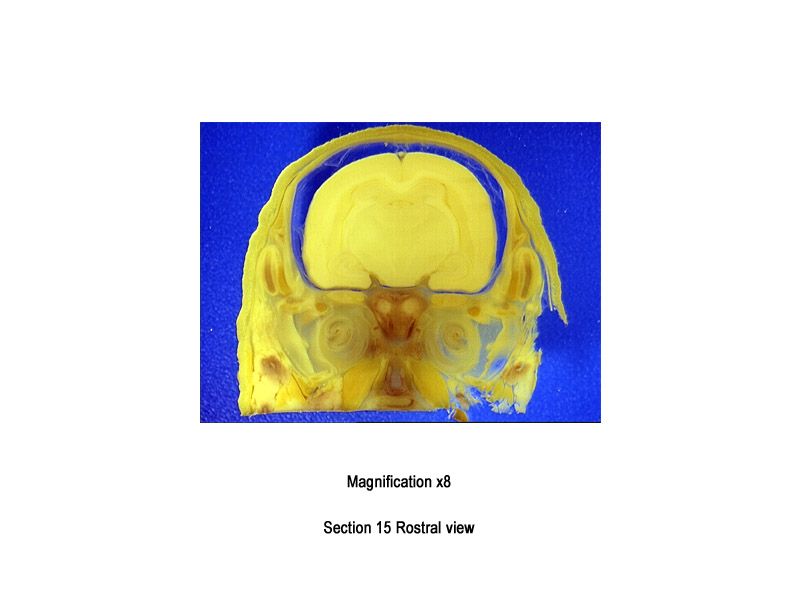

The images below show the normal appearance of Bouin's fluid fixed head sections in specimens at Day 29 of gestation (day mating observed = Day 0).

It is essential that both sides of each section is examined so that structures that exist is several sections can be visualised by the examiner in their mind as 3D.